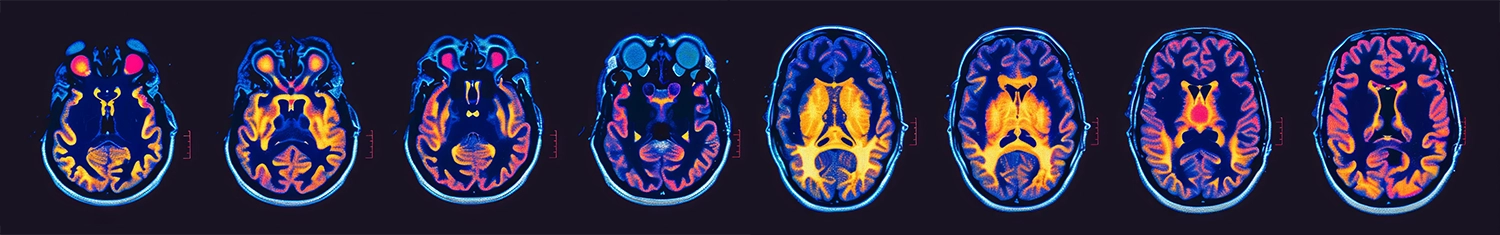

- Imaging tests: Magnetic resonance imaging (MRI) is the most common and detailed imaging technique used to detect brain tumors. Computed tomography scans may also be used in certain cases

- Advanced techniques: Functional MRI scans and molecular testing provide detailed information about tumor behavior and genetic mutations